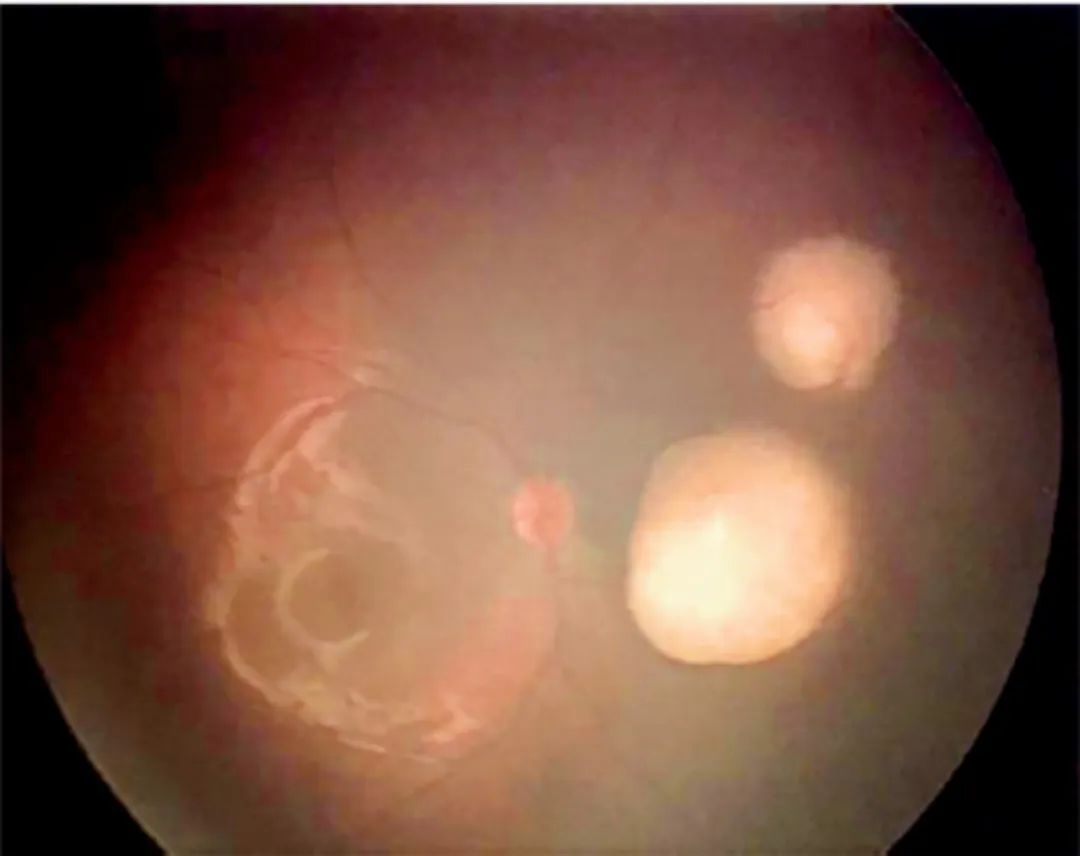

眼科小鼠